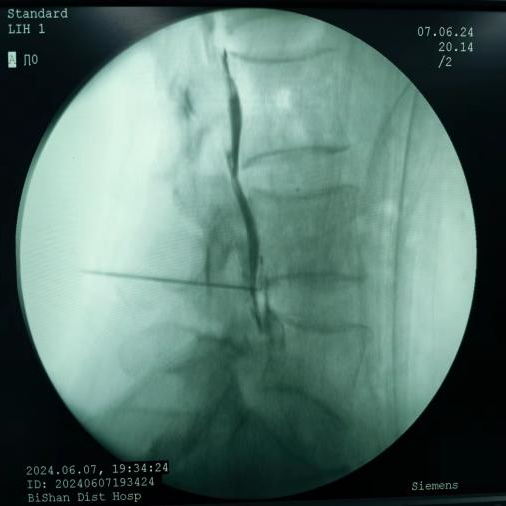

脊髓电刺激植入术:将电极植入脊柱附近硬膜外腔,通过电流刺激脊髓,阻断疼痛信号传至大脑,有效治疗慢性顽固性神经痛。

脊髓电刺激植入术